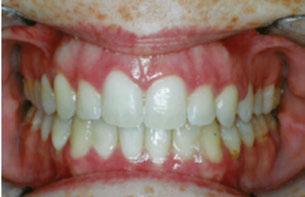

Figure 2: Initial lower occlusal

Figure 1: Initial center photo

Figure 3: Initial right buccal

This case involves a 13-year-old female patient with a complex malocclusion that includes multiple dental and skeletal issues. During the initial consultation, clinical evaluation showed severe maxillary crowding along with generalized spacing in the mandibular arch. The patient’s occlusal relationships were asymmetric, with a Class I molar relationship on the right side and a Class II molar relationship on the left. Notably, an anterior crossbite was observed, further complicated by a narrow, V-shaped maxillary arch — a common presentation that often exacerbates anterior-posterior discrepancies and limits functional occlusion. The patient also demonstrated poor oral hygiene, which is a key indicator of an indirect bonding system that does not reduce excess flash. ODB is superior in flash reduction, by being able to remove excess adhesive from three sides of the bracket instead of competitors who only remove adhesive from one side of the bracket. The presence of adhesive around brackets contributes to surface roughness which leads to plaque accumulation.1 Flash reduction will be very important for every patient’s orthodontic success (Figures 1-3).